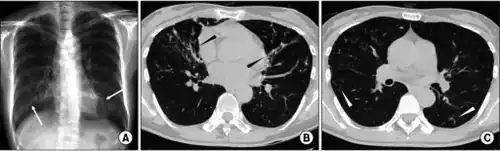

| Fibrothorax caused by infection with M lentiflavum. | |

Bronchiectasis and nontuberculous mycobacterial lung disease caused by Mycobacterium lentiflavum